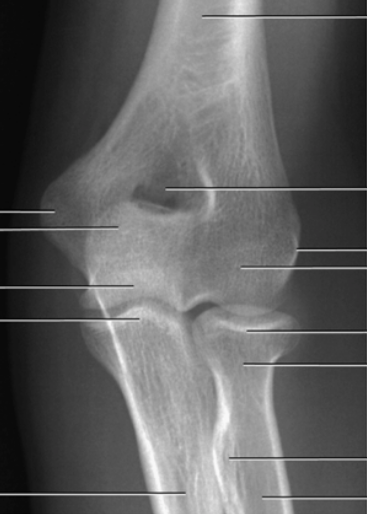

what do you see?